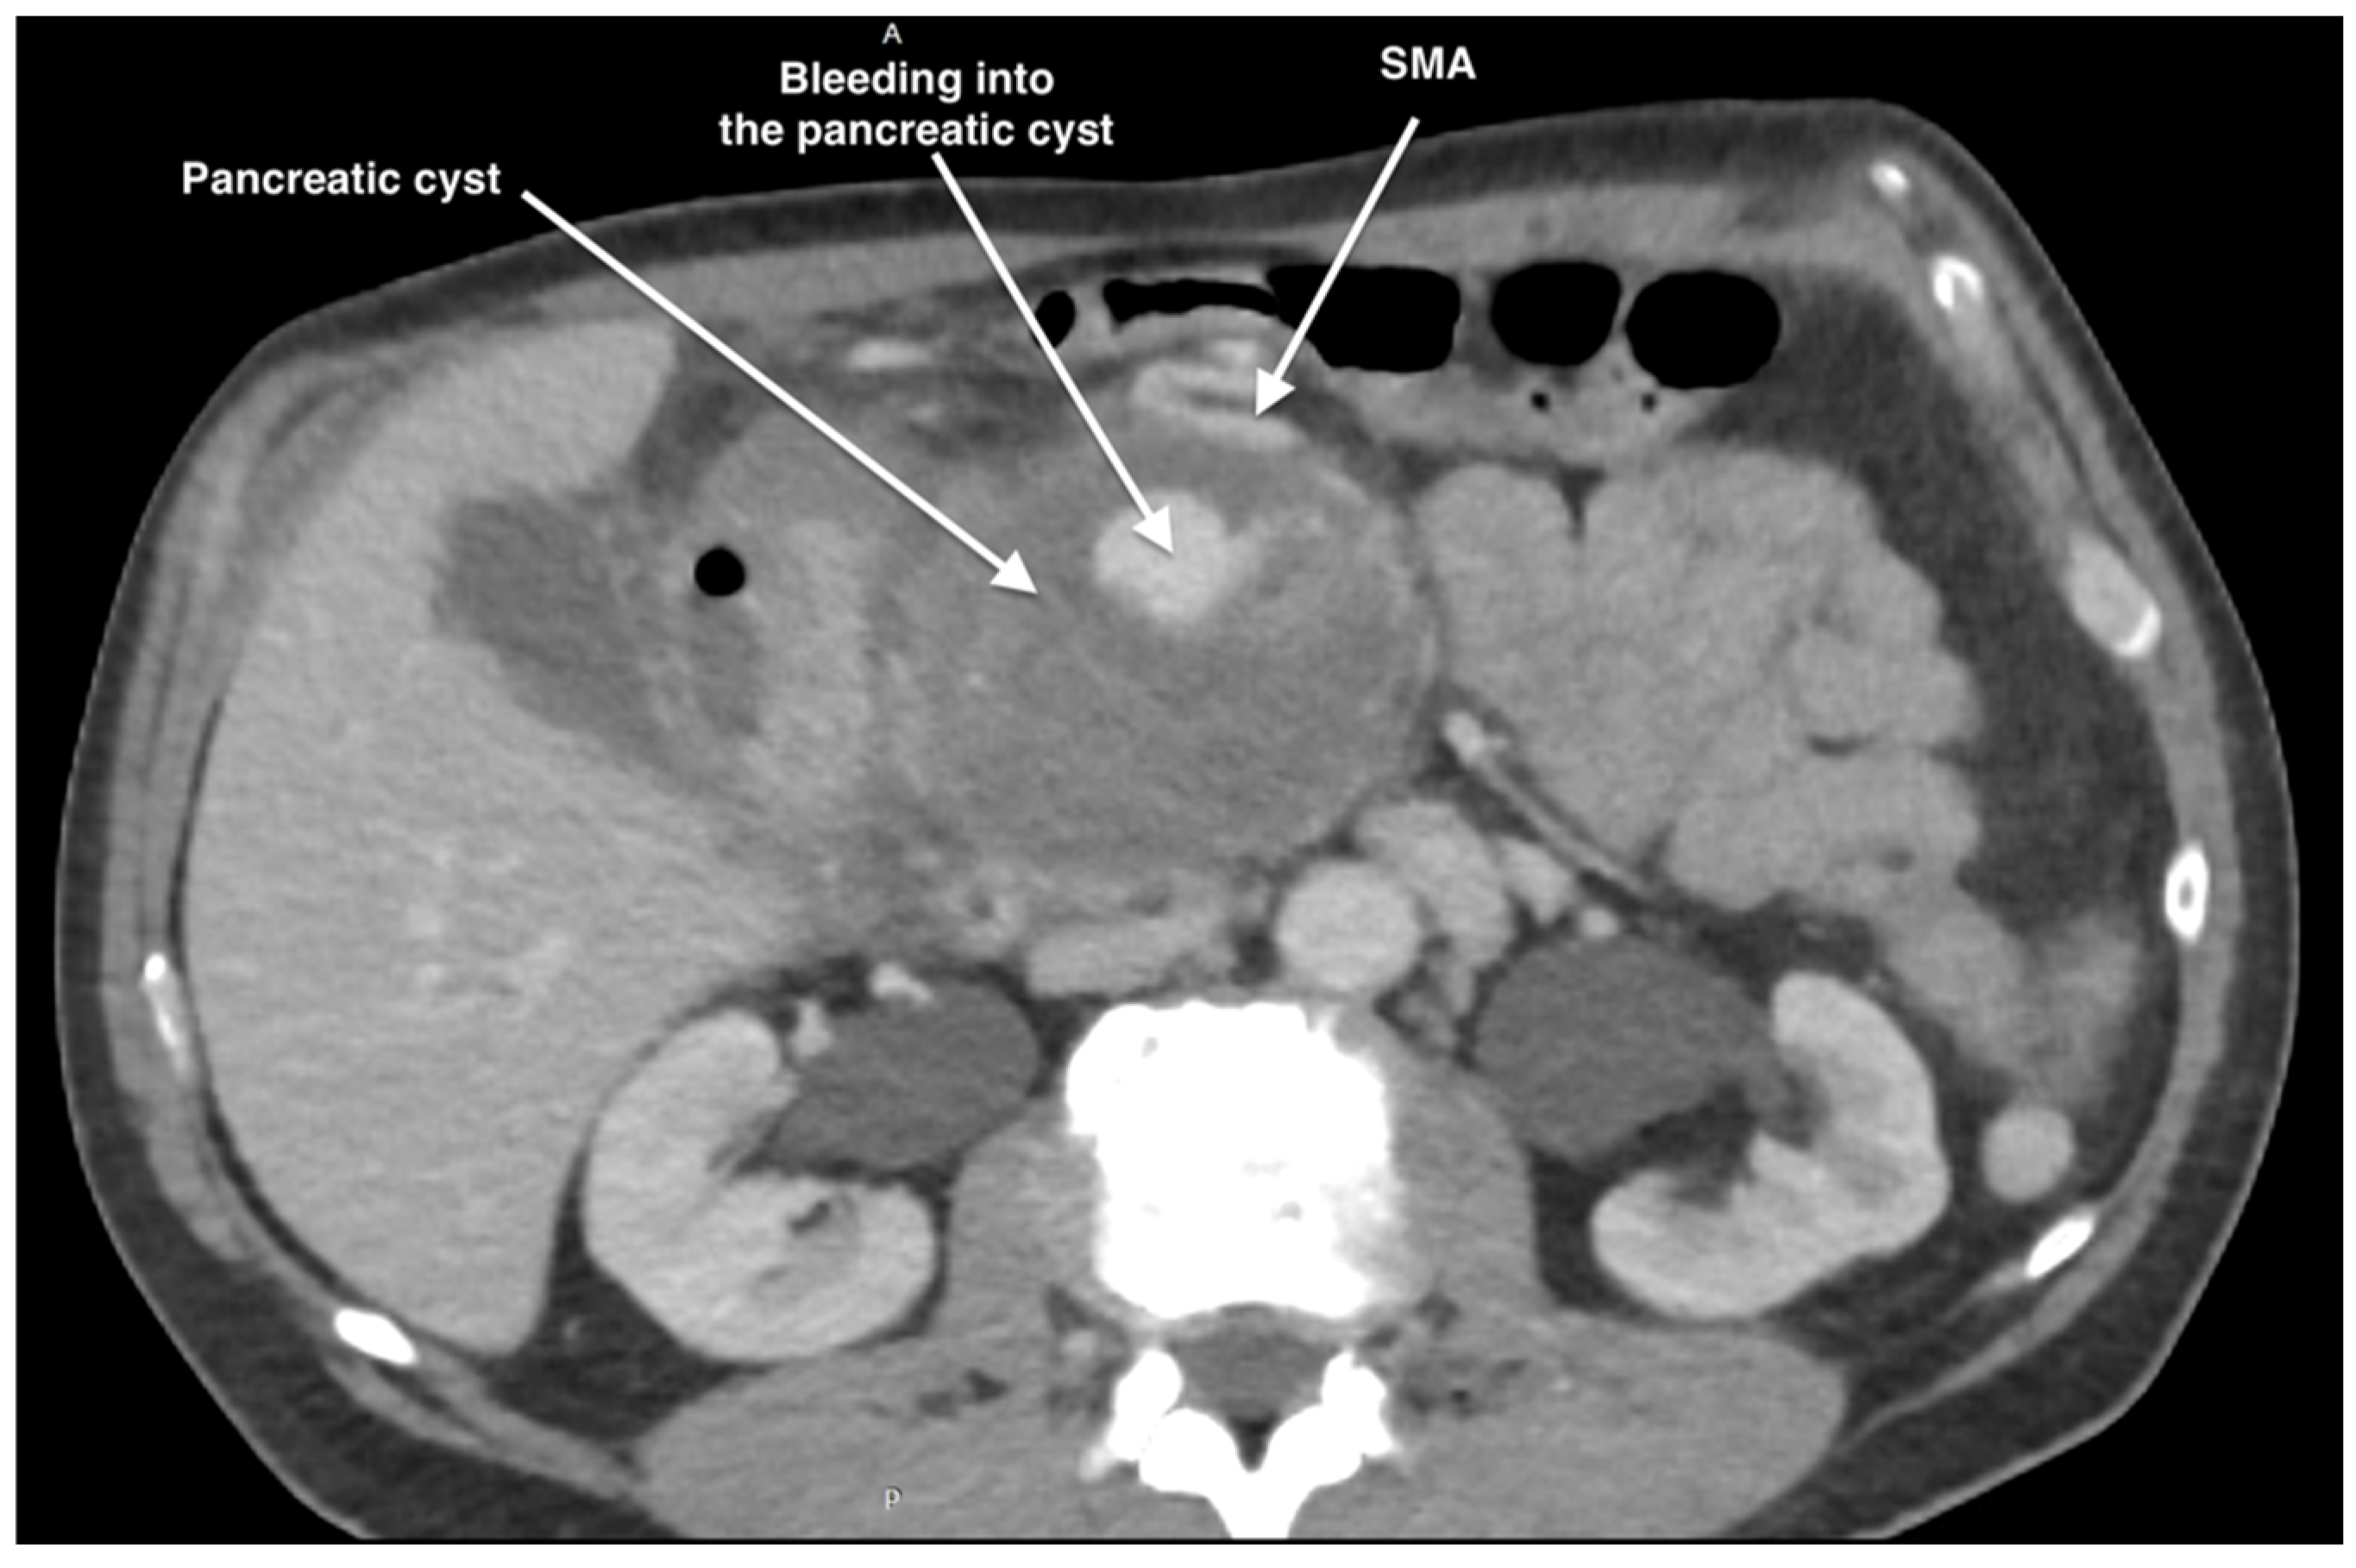

2. Case Report